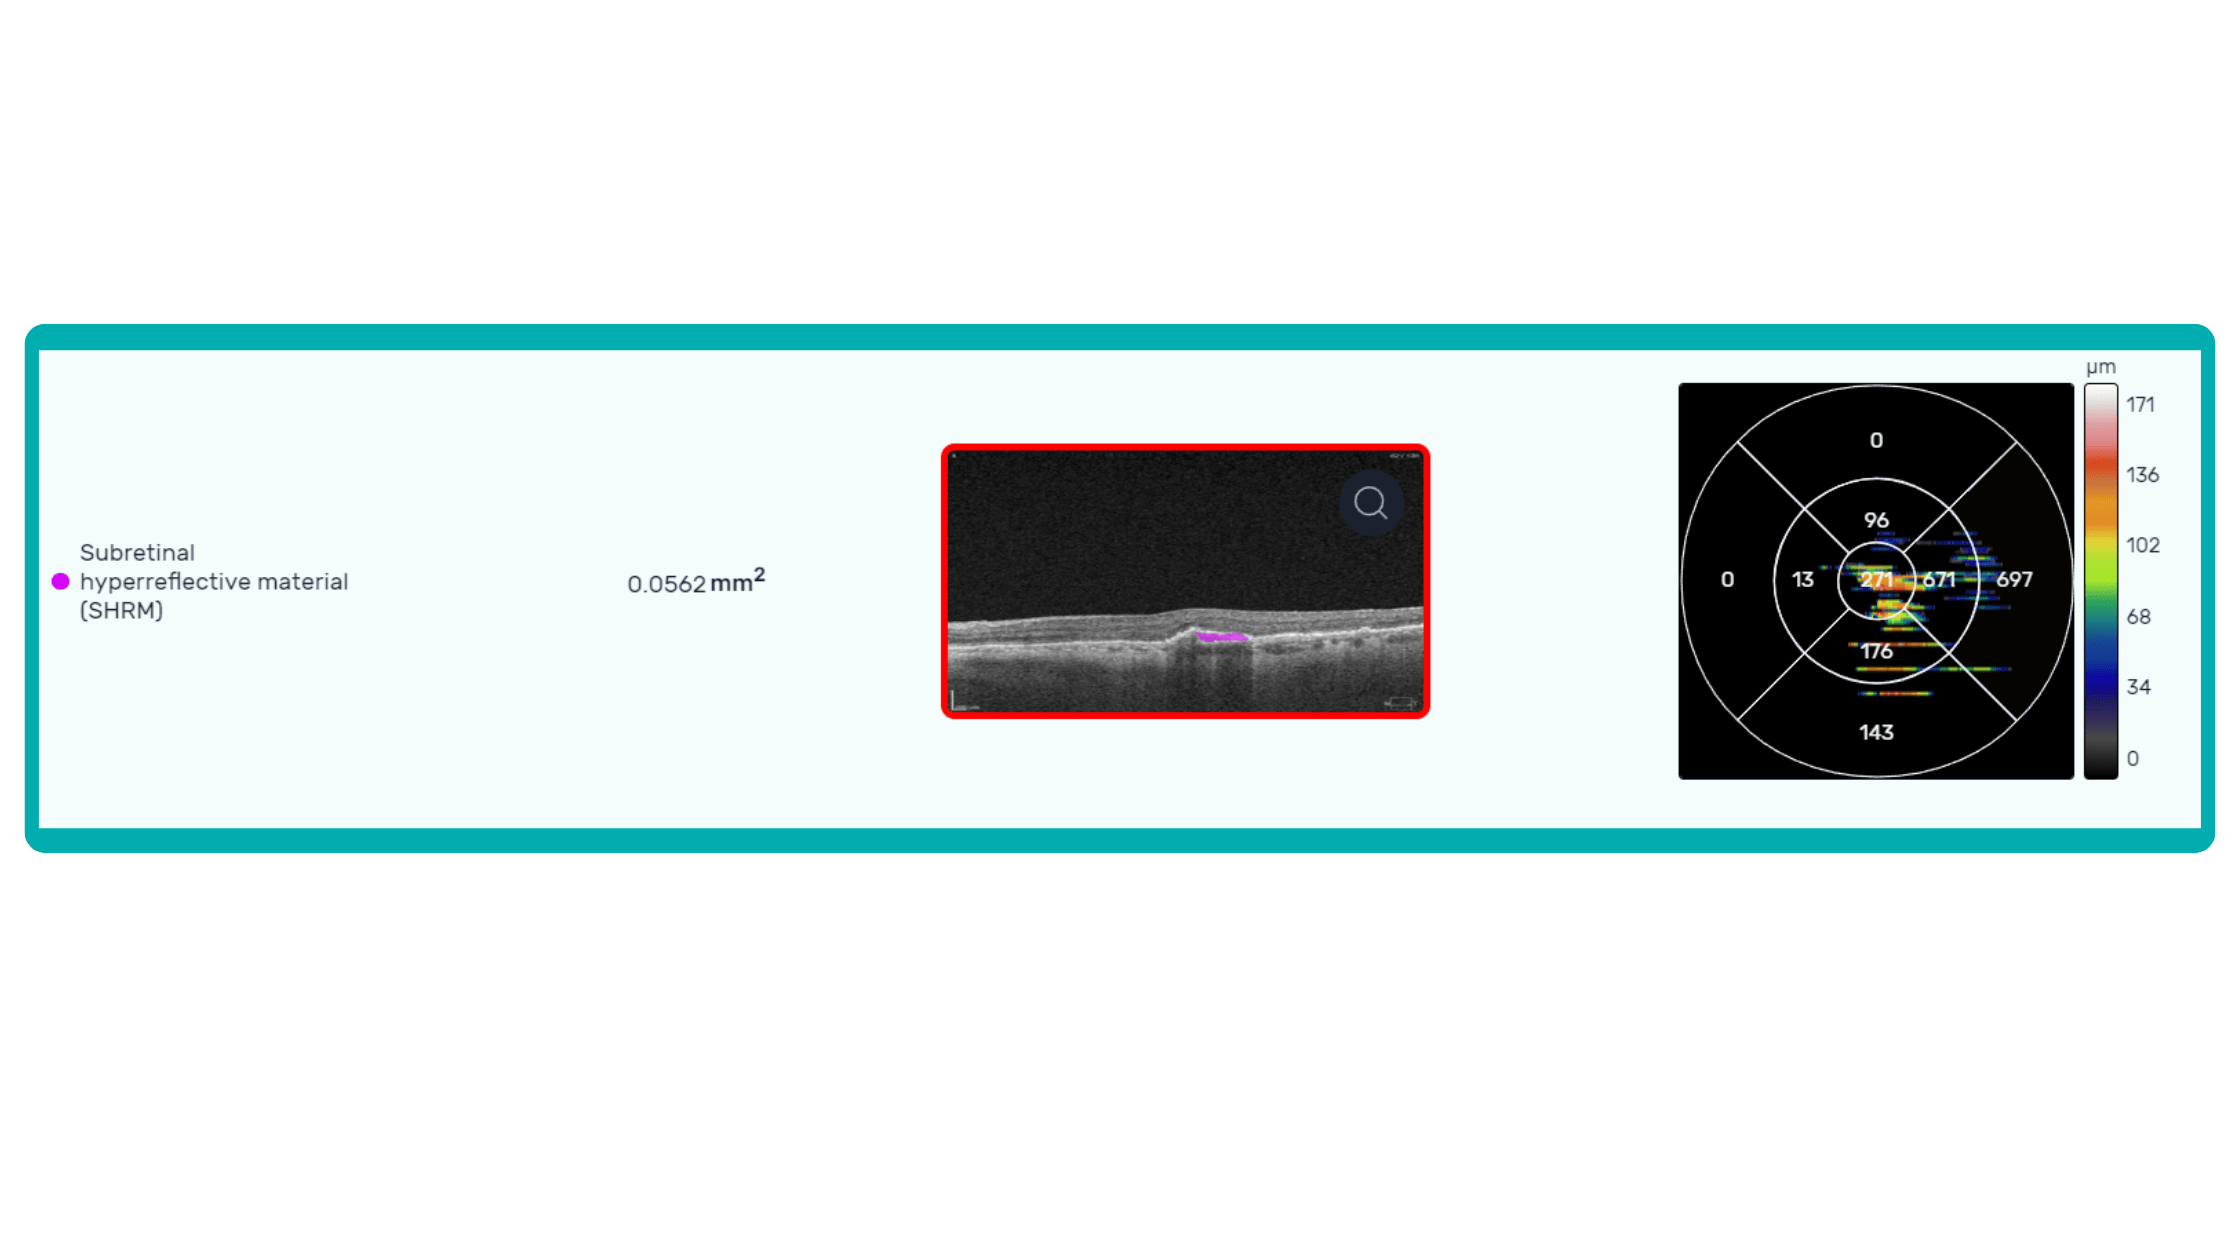

OCT is a valuable imaging tool for visualizing subretinal hyperreflective material (SHRM). It can automatically identify and quantify SHRM and fluid and pigment epithelial detachment to calculate the overall risk of worsening visual outcomes associated with SHRM.

Subsequent follow-up visits will then display the most relevant picture, highlighting the most pertinent biomarkers for tracking a particular pathology (wet AMD in our example) and comparing their volume, progression, or regression through visits.

Another helpful option is retinal layer segmentation, which focuses solely on the retinal layers of interest for the specific case.

This level of customization empowers clinicians with a comprehensive yet targeted view of the patient’s condition. It saves time from manually detecting anomalies on scans and facilitates informed decision-making and personalized treatment plans.

Color-coded OCT reports for pathologies and their signs, severity grading, and pathology progression over time within its OCT analysis highlight the littlest bits that a patient’s unprepared eye would miss otherwise. With follow-up visits, patients can see what’s happening within their eyes and track the progress of any conditions during treatment.

Systems like Altris for pathology detection and segmentation enabled automated disease characterization and longitudinal monitoring of therapeutic response in AMD. Multiple studies have demonstrated the value of volumetric fluid characterization, compartment-specific OCT feature evaluation, and subretinal fibrosis and hyperreflective material quantification.

A recent study demonstrated that quantitative improvement in ellipsoid zone integrity following anti-VEGF therapy for DME significantly correlated with visual function recovery. Furthermore, novel imaging biomarkers, such as the retinal fluid index (RFI), are emerging as tools for precisely monitoring treatment response. Studies have shown that early RFI volatility can predict long-term instability in visual outcomes after treatment.

Building on these advancements, researchers are now exploring the relationship between imaging biomarkers and underlying disease pathways. A recent study linked levels of various cytokines, including VEGF, MCP-1, and IL-6, with specific OCT-derived biomarkers like fluid parameters and outer retinal integrity.

By automating the analysis of OCT scans, AI not only streamlines the process but also uncovers subtle details and patterns that might be missed by human observation.

Enhanced by AI precision enables more accurate identification and quantification of biomarkers, leading to better patient stratification, treatment monitoring, and prediction of therapeutic responses.

An ophthalmologist’s report noting the presence of edema on an OCT scan is not the same as stating that its height and length are 411 and 3213 µm, accordingly.

Imaging biomarkers can range from simple measurements of size or shape to complex computational models, providing valuable information to complement traditional diagnostic methods. They can also determine the presence and severity of a disorder, assess its progression, and evaluate treatment response.

Parametric images, which visually represent the spatial distribution of biomarker values, further enhance the analysis of OCT scans. This combination of quantitative data and visual representation empowers clinicians and researchers to make more informed decisions about diagnosis, treatment, and disease management.